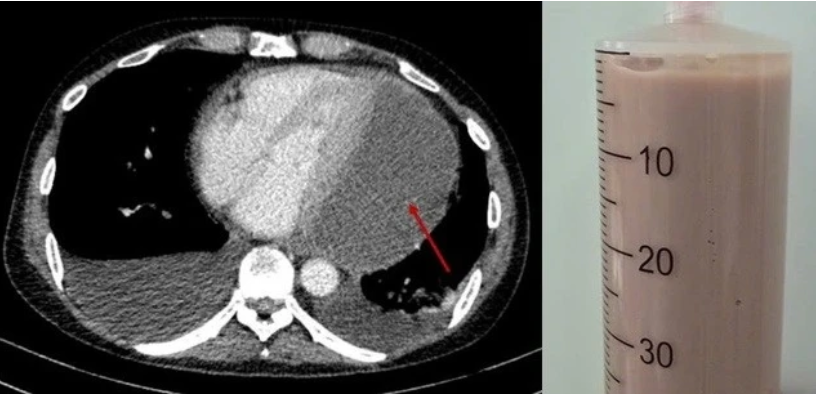

Chụp CT lồng ngực ghi nhận lớp dịch mủ chèn ép tim (mũi tên đỏ) và dịch mủ đặc rút ra được qua chọc dịch màng ngoài tim. Ảnh: BVCC.

"Đây là một ca chọc hút phức tạp và tiềm ẩn nhiều nguy cơ do khối mủ nằm ở vị trí khó tiếp cận, dịch đặc quánh. Tuy nhiên, các bác sĩ đã hút thành công 500ml mủ đặc, giảm nhanh áp lực lên tim", trưởng khoa Phẫu thuật tim - Lồng ngực mạch máu cho biết.